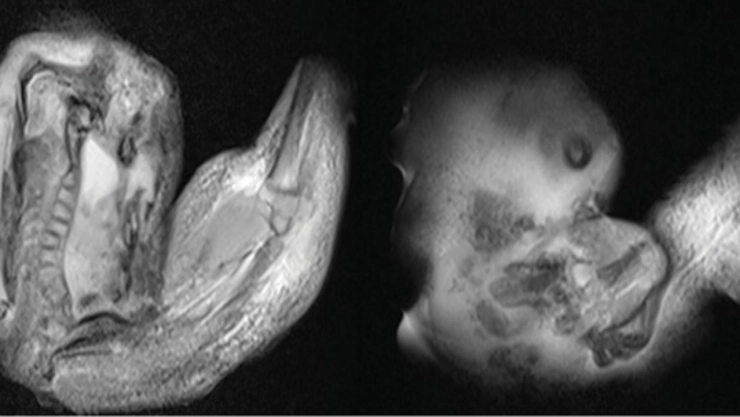

La pequeña paciente, que presentaba retraso motor y un aumento en la circunferencia de la cabeza, fue sometida a una tomografía computarizada y una resonancia magnética que revelaron la presencia de una masa anormal en su interior. Tras una compleja cirugía, los médicos lograron extraer la masa, que resultó ser un feto con columna vertebral, fémur, tibia y extremidades superiores en desarrollo.

En primer lugar, este feto en feto se descubrió "dentro de un saco similar al amnios en el ventrículo del niño anfitrión, lo que proporciona evidencia de una gemelación monocoriónica-diamniótica. Esto difiere de los gemelos unidos, que suelen ser monocoriónicos-monoamnióticos".

Los análisis genéticos posteriores confirmaron que la niña y el feto malformado eran gemelos monocigóticos, es decir, que provenían del mismo óvulo fecundado. Sin embargo, a diferencia de los gemelos comunes, este caso se caracterizó por una separación incompleta de los embriones durante las primeras etapas del desarrollo.